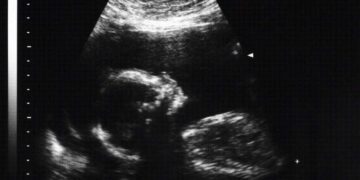

Read moreThe amniocentesis It is a study that is carried out during pregnancy, normally between weeks 16 and 22. It allows extracting information about the baby, in order to study possible...